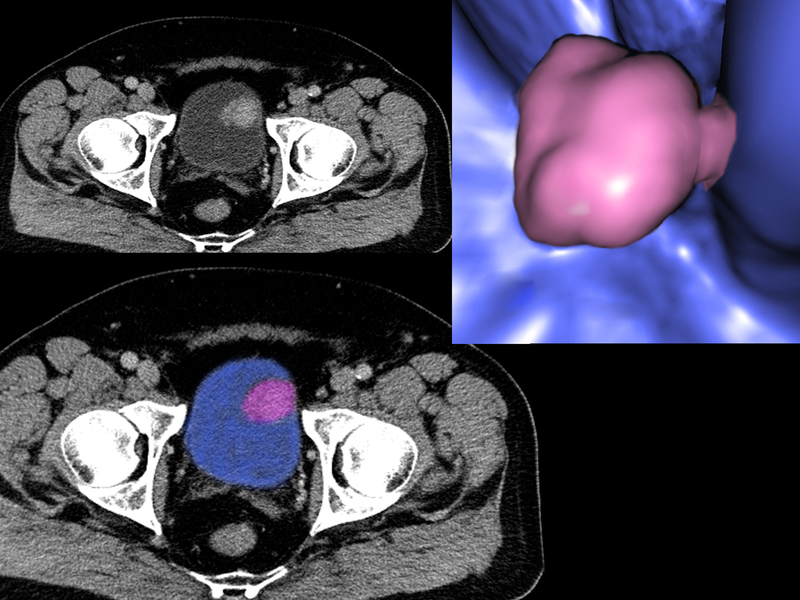

Aguilar and his group worked with the Purdue teams led by Timothy Ratliff and Deborah Knapp to test their solution in dogs with bladder cancer who had run out of other treatment options. They found this new agent decreased the tumor size without causing any other side effects in the animals.